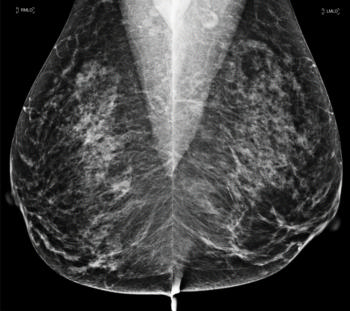

Figure 1. Images in a 55-year-old screening participant. (a, b) Normal digital full-field mediolateral oblique (a) and craniocaudal (b) mammograms (BI-RADS category 1) show a heterogeneously dense breast (ACR category C). (c) Screening ultrasound image shows normal findings (BI-RADS category 1). (d) MR-guided biopsy enabled us to confirm the presence of an invasive high-grade triple-negative cancer (no special type [NST], pT1b, N0, M0). (d) Breast MR image shows a suspicious enhancing mass (arrow) in the left breast (BI-RADS category 5).E

Figure 3. Normal digital full-field mediolateral oblique mammogram (BI-RADS category 1) show a heterogeneously dense breast (ACR category C).

Figure 4. Normal digital full-field craniocaudal mammogram (BI-RADS category 1) show a heterogeneously dense breast (ACR category C).